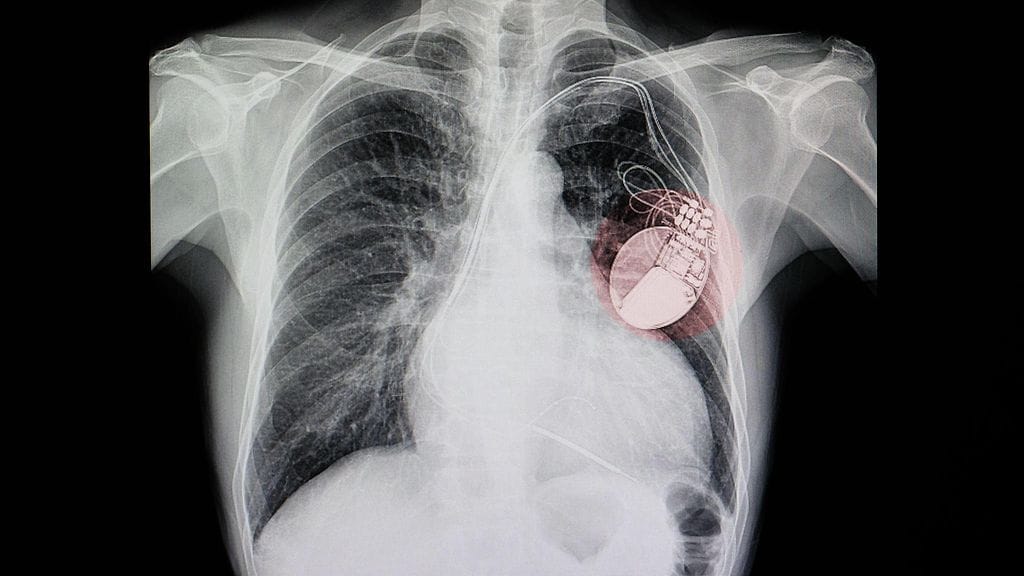

Useita lääkäreitä epäillään jopa sadoista leikkauksista, joissa kuolleilta potilaita kerättiin sydäntahdistimien kaltaisia lääketieteellisiä implantteja ja niitä asennettiin eläville potilaille Romaniassa, kertoo muun muassa The Guardian.

Yhden lääkäreistä epäilleen johtaneen verkostoa, joka otti sydänimplantteja kuolleilta potilailta ilman potilaan tai tämän omaisten suostumusta. Implantit uudelleenkäytettiin sen jälkeen asentamalla ne eläville potilaille.

Syyttäjän mukaan toiminta aiheutti kierrätetyn implantin saaneille potilaille vakavan riskin.